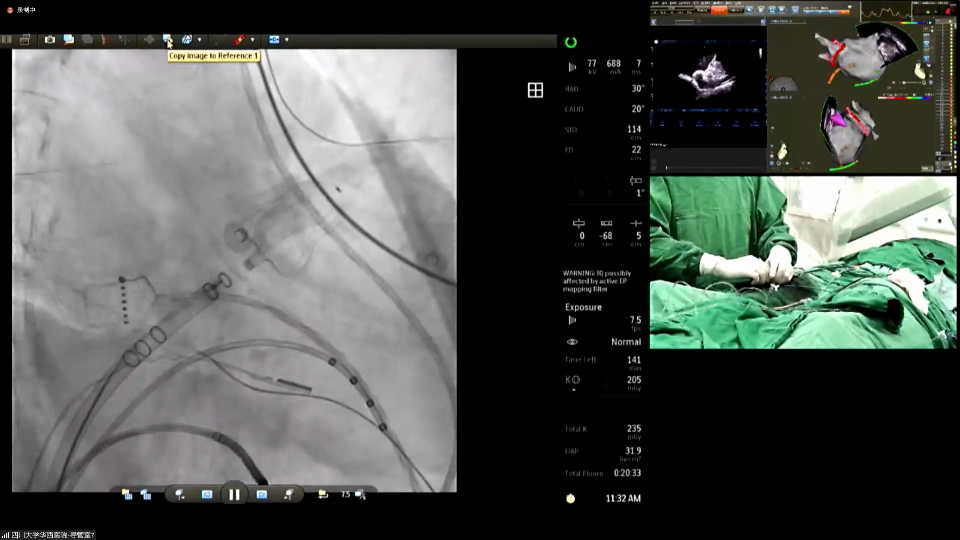

在波科远程带教直播机支持下,付华教授团队为与会专家呈现了一场精彩的射频消融+左心耳封堵“一站式”手术演示。在心脏三维标测系统的指导下,术中先进行射频消融术,然后在心腔内超声(ICE)的指导下进行房间隔穿刺。通过精准调控穿刺鞘管位置,顺利完成房间隔穿刺,取得良好的同轴性。经造影评估,显示心耳形态及大小,选择合适尺寸的WATCHMANFLX64封堵器并缓慢推送输送系统至心耳内,形成FLXBALL。采用退鞘法和进伞法相结合进行封堵。经牵拉测试确认封堵器充分膨胀且位置稳定,ICE和造影复查满足“PASS”原则。最后,将封堵器完全释放,再次进行ICE和造影评估,显示无残余反流且封堵完全。手术圆满结束。